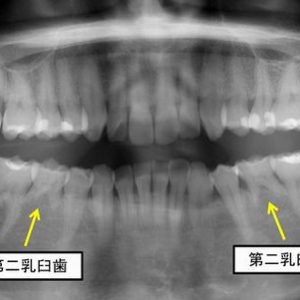

続きを読む30代女性の症例です。下あごの左右第二小臼歯が先天的になく大きな乳歯が2本残存している状態です。永久歯に比べて根っこがかなり短いのですが、動揺もなく咬み合わせにも大きな問題がないので、このまま経過観察となります。